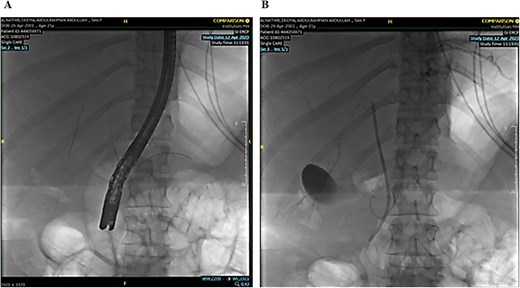

A single segmental biliary stricture was identified in the common hepatic duct. Biliary sphincterotomy was conducted as a form of post-ERCP prophylaxis, and a plastic stent was placed in the right hepatic duct and ventral pancreatic duct, as shown in Fig. 5. Visualization of the biliary tree confirmed the patency of the ducts.

Demonstrating placement of a plastic stent in the right hepatic duct and ventral pancreatic duct as post-ERCP prophylaxis.